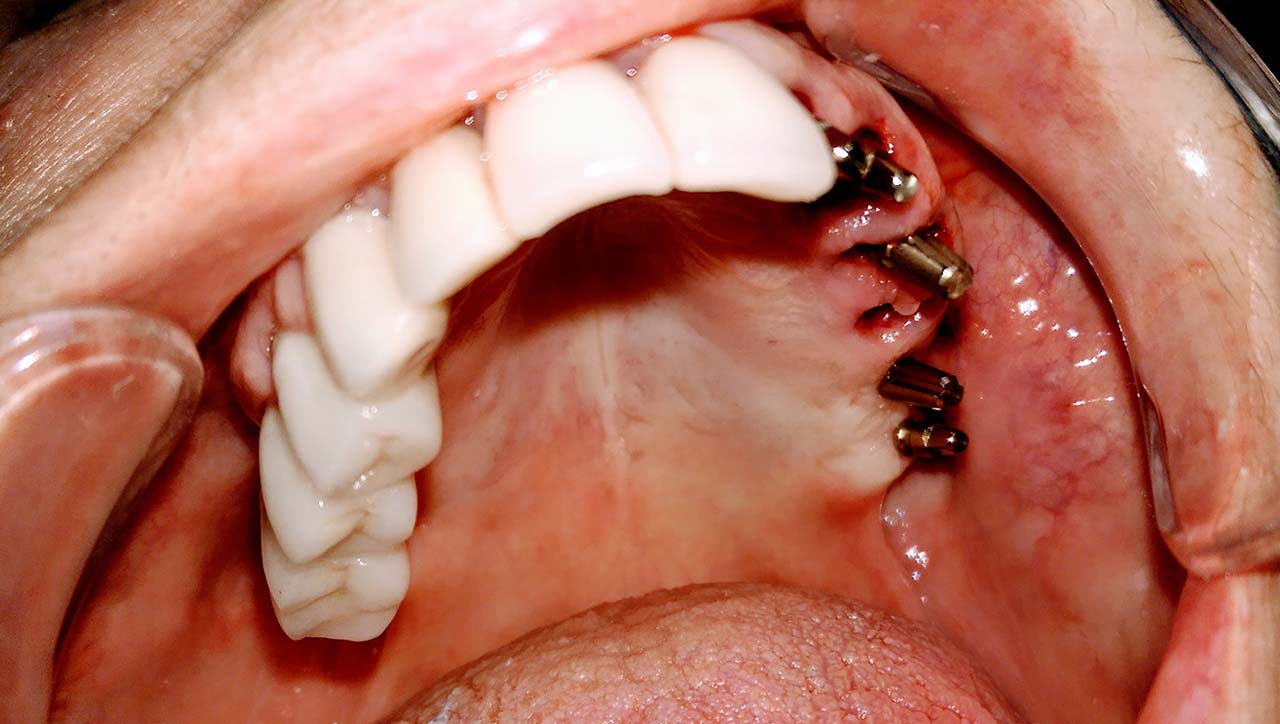

Teljes fogatlanság helyreállítása 2 nap alatt

Teljes fogatlanság helyreállítása 2 nap alatt azonnal terhelhető svájci IHDE implantátumokkal és PMMA műanyag hidakkal. Intraorális szkennerrel vettünk lenyomatot az implantáció után, és erre a digitális mintára készítette el a fogtechnika a hidak digitális tervezését, majd faragta ki műanyagból. Ezt a gyors munkát az azonnal terhelhető implantátumok és a digitális lenyomat, tervezés segítségével tudtuk megcsinálni mindössze 2 nap alatt. Dr. Kelemen Péter és a Symbion Fogtechnika munkája.